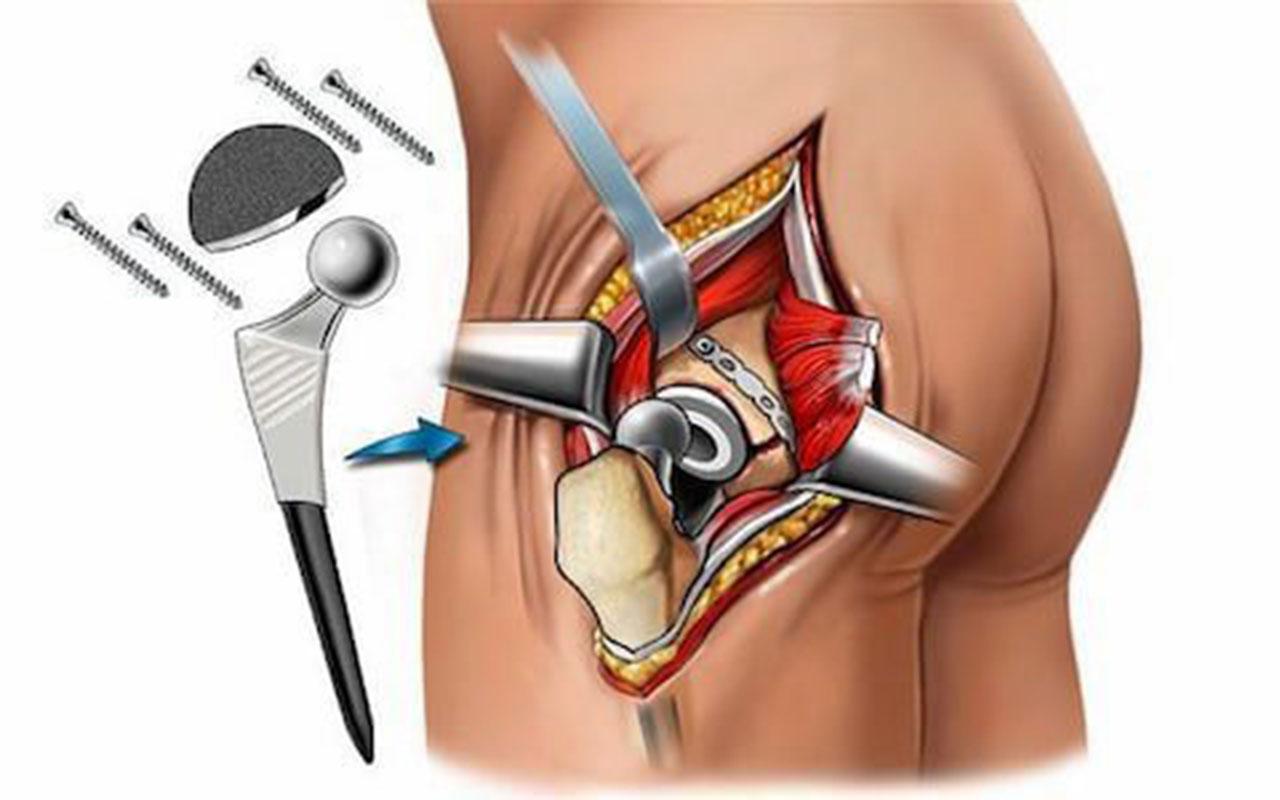

Замена таз сустава

Замена таз сустава 113 фотографий